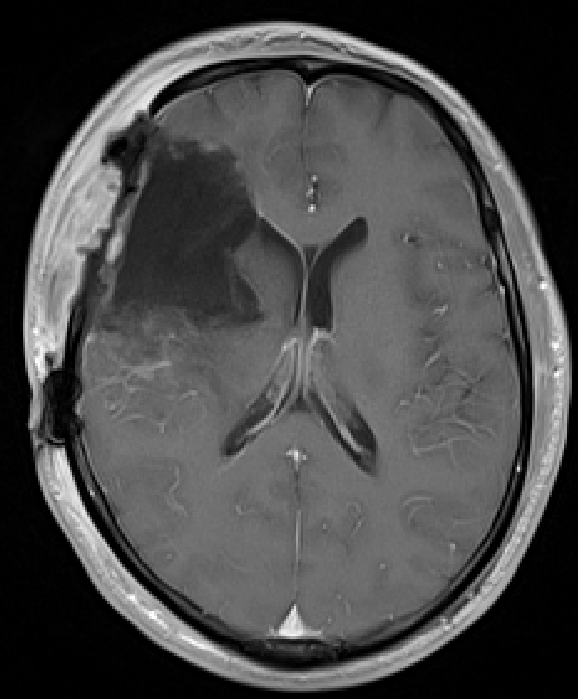

王先生隨即來到惠州三院神經(jīng)醫(yī)學(xué)中心神經(jīng)外科,查了頭顱CT顯示:右側(cè)額顳島葉及右側(cè)基底節(jié)區(qū)大片狀異常密度影。很不幸,醫(yī)生的結(jié)論跟他預(yù)想的一樣,需要再次手術(shù)治療。因?yàn)樾湃危俅巫∵M(jìn)了神經(jīng)外科病房,決定與膠質(zhì)瘤決戰(zhàn)到底。

術(shù)前術(shù)后MRI增強(qiáng)